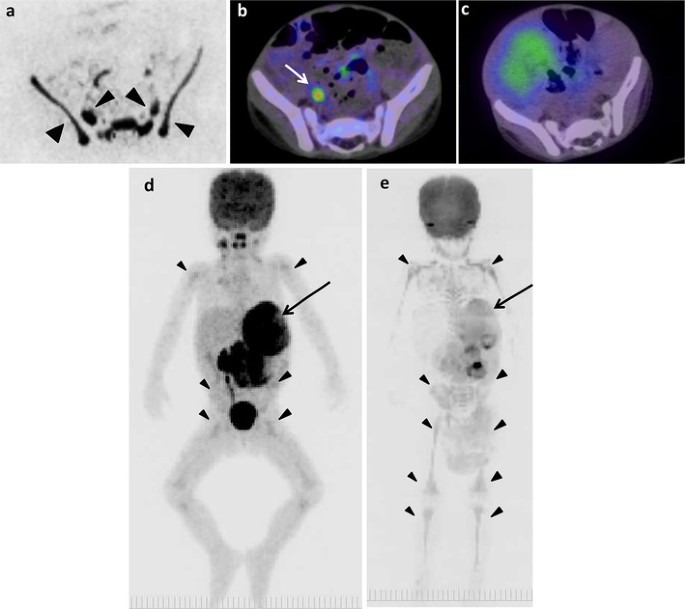

Fig. 2

figure 2

Metastasis in left temporal bone of skull of 1 year and 7 months old girl (patient 6). a 18F-FDG PET/CT. b DWIBS. c 123I-MIBG scintigraphy/SPECT-CT. d Bone scintigraphy/SPECT. e CT. Arrows show metastasis (ae). Arrowhead shows false-positive images in sphenoidal bone (b)

The example false-positive images in various bone segments by DWIBS are shown along with the negative results by 18F-FDG PET/CT, 123I-MIBG scintigraphy/SPECT-CT, and bone scintigraphy/SPECT in Figs. 1, 2, 4, 5 and 6. Diffuse intensive false-positive signals by DWIBS are seen in pelvic bones (iliac and sacral bones) (Fig. 4a). Faint diffuse false-positive signals are seen in various bones (Figs. 5, 6).

Fig. 4

figure 4

The original lesion in left adrenal gland and false-positive images of skeletons of 2 years and 2 months old boy (patient 8). a DWIBS. b 18F-FDG PET/CT. c 123I-MIBG scintigraphy/SPECT-CT. The MIP of 18F-FDG PET (d) and DWIBS (e). Long arrows show the original lesion (d, e). Arrowheads show false-positive images in pelvic bones (a) and various bone segments (d, e). Short arrow shows 18F-FDG uptake in right ureter (b)